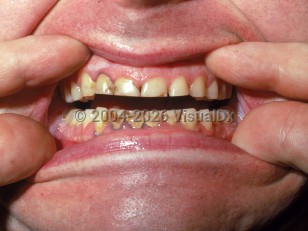

Look For